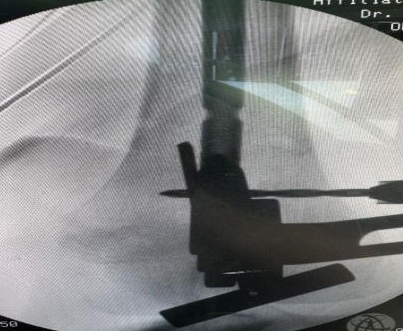

Application of correction leverage technique in primary failure of distal locking screw during antegrade femoral intramedullary nailing

He Zhiyu, Wan Zhihong, Huang Yu, Liu Anming, Wu Jiaqi, Wang Guoyou, Zhang Lei, Chen Xiaojun

2026, 30 (21):  5503-5509.  doi: 10.12307/2026.206

Abstract ( 6 )   PDF (1700KB) ( 4 )   Save

BACKGROUND: Interlocking intramedullary nail fixation is the “gold standard” for the treatment of femoral shaft fractures, and the difficulty of distal locking nail implantation has always been a difficult problem to solve.

OBJECTIVE: By comparing the clinical effects of correction leverage technique and free-hand locking nail technique, it is further explained whether the correction leverage technique can be fast and accurate. The distal locking screw of femoral intramedullary nail was placed without direct X-ray radiation exposure, so as to solve the difficulty of distal locking screw placement.

METHODS: A total of 52 patients with femoral shaft fractures who experienced difficulty in distal locking screw placement during femoral interlocking intramedullary nail fixation at the Department of Orthopedics, Affiliated Traditional Chinese Medicine Hospital of Southwest Medical University between July 2022 and September 2024 were enrolled. Participants were randomly divided into two groups according to the implantation scheme: the correction leverage group (n=26) underwent the compression bar technique, while the freehand locking nail group (n=26) received conventional freehand locking screw placement for distal femoral intramedullary nail fixation. The distal locking screw placement time, X-ray projection times and first distal screw placement accuracy were compared between the two groups.

RESULTS AND CONCLUSION: (1) The distal locking nail placement time in the correction leverage group was significantly shorter than that in the freehand locking nail group (t=-4.136, P < 0.001), with a statistically significant difference. (2) The number of X-ray fluoroscopies in the correction leverage group was less than that in the freehand locking nail group (t=-19.696, P < 0.001), with a statistically significant difference. (3) In terms of the accuracy of the first nail placement in both groups, the correction leverage group (100%) was higher than the freehand locking nail group (71%), with a statistically significant difference (x2=5.253, P < 0.05). (4) The results show that the correction leverage technique has the advantages of fast nail locking, high accuracy, and low X-ray radiation compared with pure freehand nail placement. This technique does not require other auxiliary equipment and is highly maneuverable. Further clinical validation is warranted for its widespread application in femoral shaft fracture fixation with interlocking intramedullary nailing.